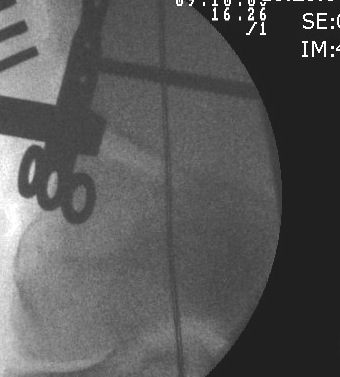

Osteotomy

- insert guide wires

- proximal lateral to distal medial

- proximal 1 - 2 cm above flare of lateral condyle

- aim towards adductor tubercle

- risk of medial hinge fracture reduced if osteotomy at or distal to adductor tubercle

- ensure these are perpendicular to the femoral shaft in the sagittal plane

- above patellofemoral joint and posterior condyles

- stop osteotomy 1 cm short of medial cortex